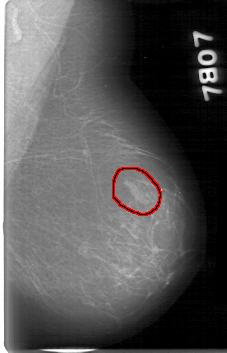

D_4020_1.LEFT_MLO

FILE: D_4020_1.LEFT_MLO.OVERLAY

TOTAL_ABNORMALITIES 1

ABNORMALITY 1

LESION_TYPE MASS SHAPE LOBULATED MARGINS OBSCURED

ASSESSMENT 0

SUBTLETY 2

PATHOLOGY BENIGN

TOTAL_OUTLINES 1

BOUNDARY